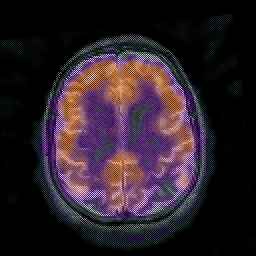

Alzheimer's disease: overlay -- Slice #36

[Home][Help][Clinical] Slice 36